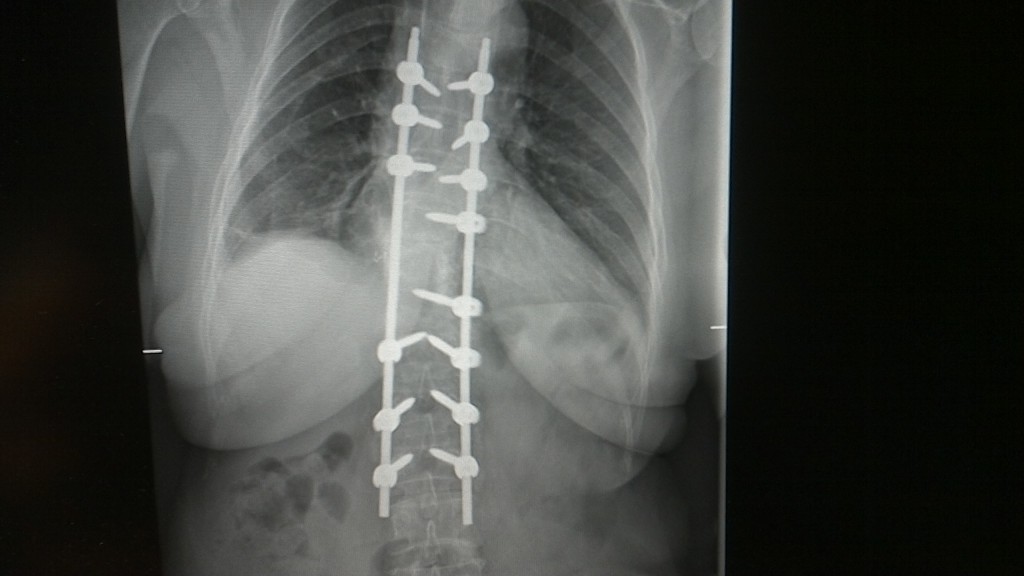

Wenn wir älter werden, nehmen die Verschleisserkrankungen zu. Und die Wirbelsäule verliert oft die gerade, aufrechte Struktur und wird krumm und krümmer. Im Röntgenbild sehen wir oft ganz verschiedene Verschleisssituationen nebeneinander. Da die Wirbelsäule aus verschiedenen Bewegungssegmenten besteht, muss der Wirbelsäulenchirurg genau wissen, woher der Schmerz kommt. Würde man sich…